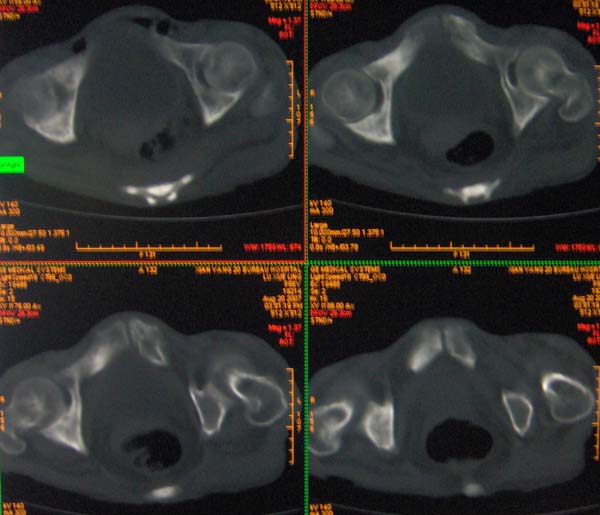

以下是引用ybing在2007-8-22 20:31:00的发言:[br]左侧髂骨溶骨样破坏;软组织肿块形成;其内未见肿瘤骨考虑纤维肉瘤或滑膜肉瘤不除外转移瘤

以下是引用qiushi在2007-8-22 21:39:00的发言:[br]双侧髂骨、骶骨侧快呈溶骨样骨质破坏,边缘模糊,左侧髂骨见骨折线,左侧髂部见软组织块影。考虑骨纤维肉瘤(中央型)伴病理性骨折,不排除骨髓瘤。建议本--周氏蛋白检查。[br] 鉴别点:[br] 骨纤维肉瘤,中央型者示边缘模糊的囊状溶骨破坏,一般无骨膜反映,可膨胀变形,突破骨皮质可形成软组织肿块,或并发病理性骨折。[br] 骨髓瘤,常表现为广泛的骨质疏松,皮质变薄或破坏,呈粟栗状、穿凿状、鼠咬状骨质破坏,边缘清晰,周围无硬化。[br] 骨转移瘤(溶骨型),表现为虫噬样、泡沫状圆形或卵圆形破坏区,很少出现软组织块影。[br][br][本贴已被 qiushi 于 2007-8-23 6:20:19 修改过]